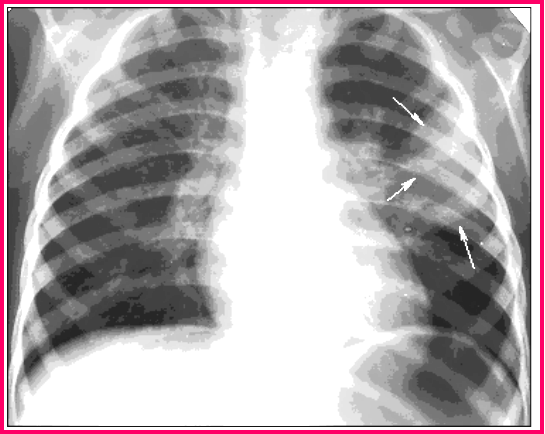

13个小时前后胸片对照

金黄色葡萄球菌性肺炎

(staphylococcal pneumonia)

一、起病急,病情严重,发展迅速

二、毒血症状明显,如高热、面色苍白、气促 、纳 呆、腹胀等,可有腥红热样或荨麻疹样皮疹

三、易形成脓胸、脓气胸、肺大泡、纵隔气肿、皮下气肿等并发症,易变性是金葡菌的X线特征

四、局限能力低下者散播成败血症和形成迁徙性化脓性病灶

五、半数婴幼儿WBC ↓

六、对抗生素耐药性强,病程较长,常在4~6周以上